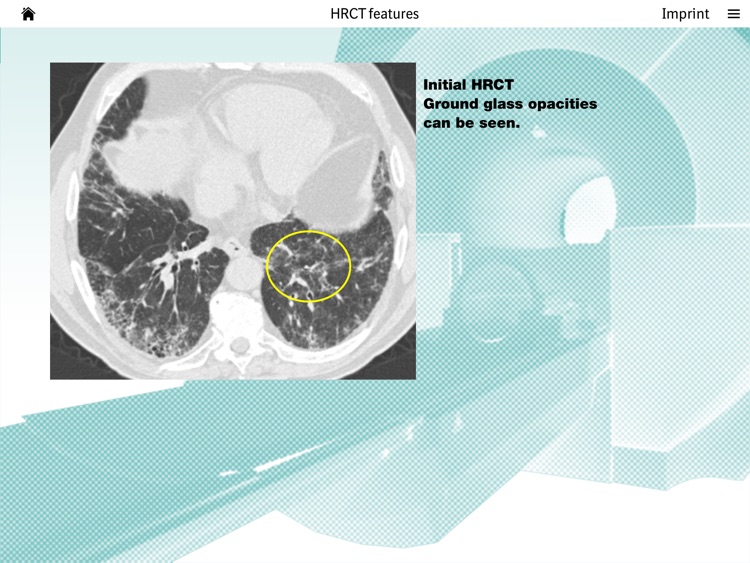

Images of ILD is a novel and unique software tool for training professional skills in interpreting CT scans of Interstitial Lung Disease (ILD) patients. Images of ILD enables you to examine real CT images of ILD patients and thereby train you ability to recognise typical patterns. A variety of authentic cases provides insights into the specific patterns associated with different types of ILDs. The main focus of the tool is on the HRCT scan, but detailed patient information and expert opinion is also provided. A special highlight is the interactive Q&A session at the end of each case in which you can test your ability to recognise typical HRCT patterns as presented in the case. The handling of the software is intuitive and constitutes a well-structured and comprehensible e-learning tool for ILD HRCTc cases.